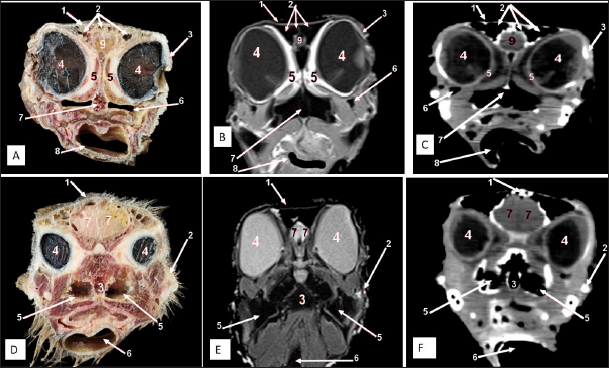

Fig. 6. Rostral-caudal cross sections of the adult ostrich head—level 1. Rostral views of A) photograph of an anatomical cross section, B) MRI and C) computed tomography images (rostral view) showing: a- Rostral nasal concha, b- Dorsal nasal recess, c- Ventral nasal recess, d- Nasal septum. Caudal views of D) an anatomical section photograph, E) MRI and F) computed tomography images showing: 1- Os nasale, 2- Os maxillare, 3- Vomer, 4- Nasal septum, 5- Infra orbital sinus, 6- Frontal sinus, 7- Mandible, 8- Tongue, a- Middle nasal concha (bulla), b- Middle nasal concha, c- Middle nasal meatus, d- Ventral nasal meatus, and e- Rostral nasal concha mucosal fold.

Fig. 7. Rostral-caudal cross sections of the adult ostrich head—level 2. Rostral views of A) photograph of an anatomical cross section, B) MRI and C) computed tomography images showing: 1- Processus.frontalis, 2- Os maxillare, 3- Vomer 4- beginning of the orbit, 5- Infra orbital sinus, a- Middle nasal concha, b- Dorsal nasal meatus, c- Ventral nasal meatus, d- Nasal septum. Caudal views of D) anatomical cross section, E) MRI, and F) computed tomography images showing: 1- Processus. frontalis, 2- Frontal sinus (separated by the median septum), 3- Lateral nasal process, 4- Processus.jugalis, 5- Nasal septum (two ridges separated by an empty groove), 6- Caudal nasal concha, 7- Ventral nasal meatus, 8- Infra orbital sinus, 9- Palate, 10- Oropharynx, 11- Laryngeal cavity, and 12- Eye ball.

Fig. 8. Rostral-caudal cross sections of the adult ostrich head—level 3. Rostral views of A) photograph of an anatomical cross section, B) MRI and computed tomography images showing: 1- Os nasalis, 2- Frontal sinus (divided by septea), 3- Lateral nasal process, 4-Os jugalis, 5- Vomer (pneumatic), 6- Nasal septum (two ridges separated by an empty groove), 7- Laryngeal cartilage, 8- Laryngeal cavity, 9- Eye ball, 10- Infra orbital sinus, 11- Choanae. Caudal view of D) an anatomical section, E) MRI and F) computed tomography images showing: 1- Os nasalis, 2- Frontal sinus, 3- Lateral nasal process, 4- Eye ball, 5- Os jugalis, 6- Pars verticalis ethmoidale, 7- Vomer, 8- Infra orbital sinus, 9-Latyngeal cartilage, 10- Tracheal lumen surrounded by tracheal cartilaginous rings.

The nasal conchae exhibited in the MRI images as bright (high or hyperintense signal intensity) to gray (low or hypointense signal intensity) structures that could be divided into three parts: rostral, middle, and caudal conchae, which correlated to the morphological examinations. In contrast, the nasal conchae could not be recognized clearly on CT images compared to those obtained after MRI (Figs. 25 B and C). The paranasal sinuses with other structures could be identified using both CT and MRI. The nasal septum and paranasal sinuses revealed a white bone border (high signal intensity), soft tissue was grey (low-to-intermediate signal intensity), and they contained black gas, so both the CT and MRI scans showed little signal intensity (Figs. 15B and C and 79B, C, E, F).